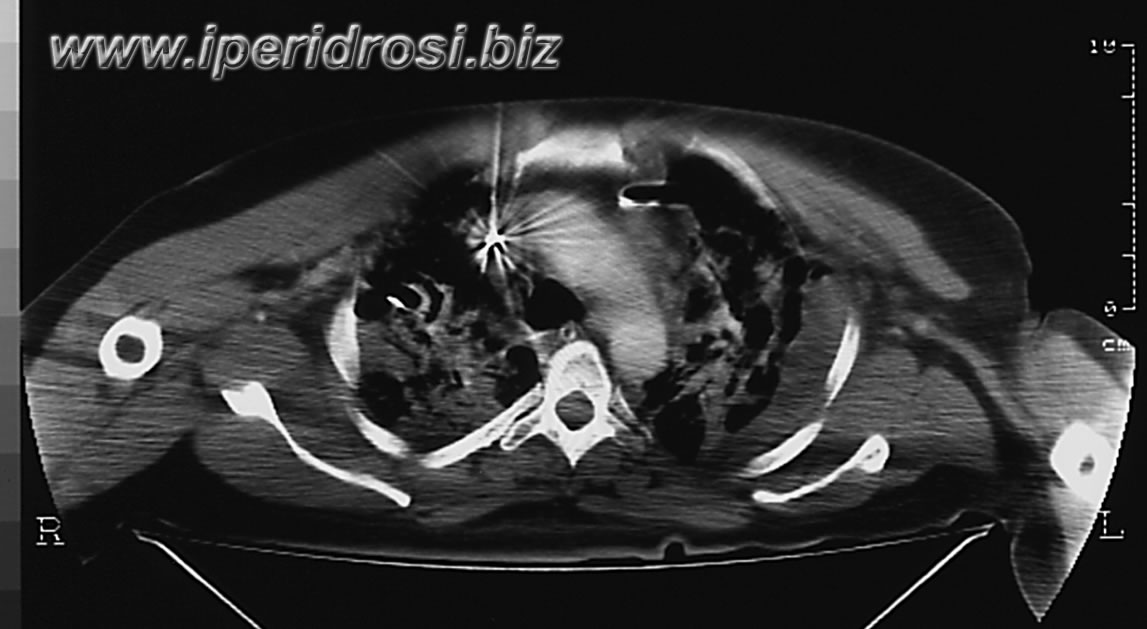

tac del giorno T 5

Al presente controllo si osserva regressione del versamento pleurico sinistro e comparsa di addensamenti interstizio alveolari diffusamente confluenti da ambo i lati. Residua piccola falda liquida peri e sotto epatica. Non falde di gas libero